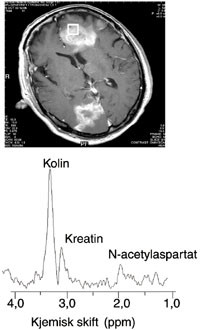

In vivo-MRS i hjernen er enklere enn i andre organer, fordi man slipper problemer med organbevegelse og fett. Figur 2 viser et spekter med lang ekkotid (135 ms) av temporallappen hos en frisk frivillig. Toppene i spekteret representerer N-acetylaspartat, kreatin og kolin. Intensiteten til toppene varierer, avhengig av området i hjernen spekteret er tatt fra. Laktat og lipider er ikke observerbare i friskt vev, men kan være detekterbare ved enkelte sykdommer (iskemi, svulster). N-acetylaspartat finnes bare i nevroner, og konsentrasjonen av denne metabolitten varierer med tettheten av nevroner i de forskjellige strukturene i hjernen. Med økende alder og ved nevrodegenerativ sykdom blir konsentrasjonen av N-acetylaspartat redusert. Kreftsvulster i hjernen er vanligvis av ikke-nevronal opprinnelse, og spektrene viser lave eller manglende konsentrasjoner av N-acetylaspartat. Ved enkelte sykdommer som hjerneinfarkt kan kreatinnivået være kraftig redusert (6). Kolintoppen er økt i maligne svulster, noe som blir forklart med økt cellemembranomsetning i tumorvev. Laktatkonsentrasjonen i hjernevev er normalt så lav at den ikke kan observeres med in vivo-MR-spektroskopi. Observasjon av laktat indikerer anaerob metabolisme, som f.eks. ved infarkt (7) og enkelte svulster (nekrotiske eller cystiske).

For at in vivo-MRS skal ha klinisk nytteverdi, må man oppnå tilleggsinformasjon til det man oppnår med MR-bildediagnostikk. Ved tumorsuspekte bildefunn gir økt kolin og redusert N-acetylaspartat i MR-spekter betydelig diagnostisk støtte til en tumordiagnose (fig 3). Her kan en kvalitativ beskrivelse av spekteret være tilstrekkelig. Innslag av laktat og lipider i spektrene er også patologisk.